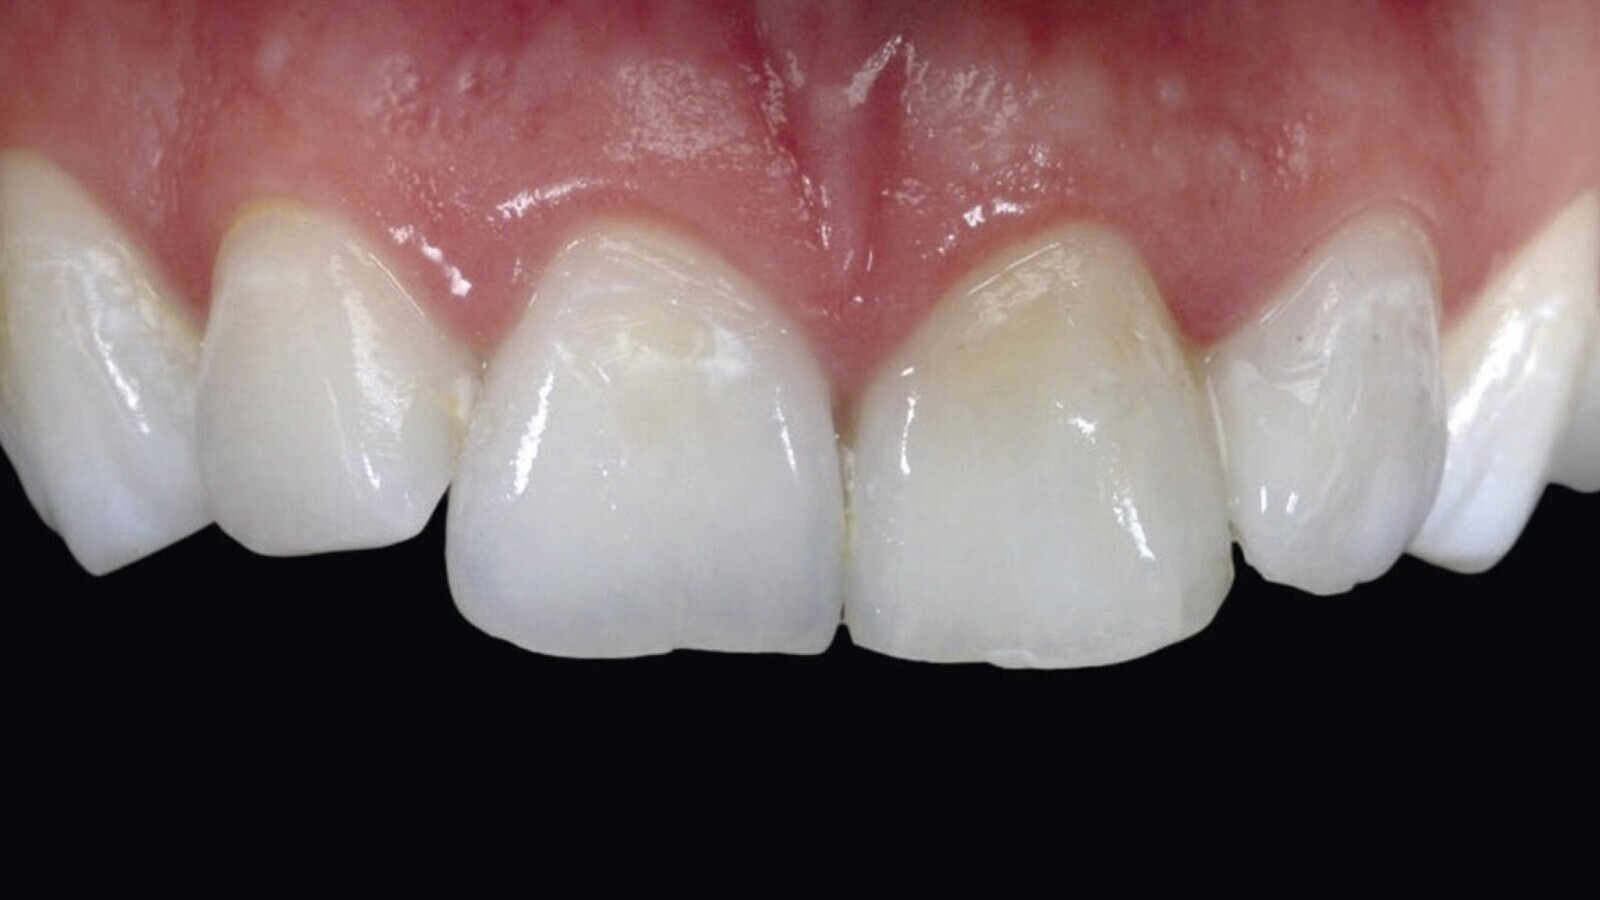

Figura 2A. Preoperatorio: cambio de coloración en la pieza 21 por residuos de obturaciones de tratamiento endodóntico anterior, donde se observan también restauraciones con resinas filtradas y restos de cálculo por higiene bucal deficiente.

Figura 2B. Postoperatorio luego del blanqueamiento interno y externo ambulatorio y el cambio de las restauraciones de resina filtradas.